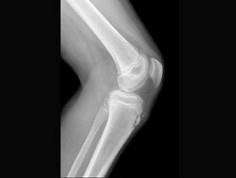

问题 符合胫骨结节骨软骨病(如图)的是 ( )

选项 A、伸膝抗阻试验阳性 B、可行局部注射醋酸泼尼松龙 C、18岁后隆起可自行消失 D、有胫骨结节疼痛,隆起 E、多见12~14岁男孩

答案 ADE